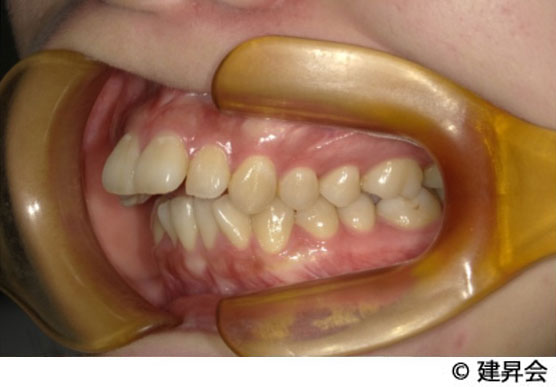

¾å²¼¤Î»õ¤¬Á°¤Ë¤Ä¤½Ð¤Æ¤¤¤ë³ú¤ß¹ç¤ï¤»¡Ê¾å²¼³ÜÁ°ÆÍ¡Ë¤Î¤ªÇº¤ß¤ò¤ª»ý¤Á¤Î´µ¼ÔÍͤξÉÎã¤Ç¤¹¡£

´µ¼ÔÍͤΤªÇº¤ß¤ÏÁ°»õ¤¬½Ð¤Æ¤¤¤ë¤³¤È¤Ç¤·¤¿¡£ -

¼£ÎÅË¡

²¼¤ÎÁ°»õÉôʬ¤òÈ´»õ¤·¡¢¥Þ¥¦¥¹¥Ô¡¼¥¹·¿¤ÎÁõÃ֤ǶºÀµ¼£ÎŤò¹Ô¤¤¤Þ¤·¤¿¡£

3ǯ´Ö¤«¤±¡¢¤´Ééô¤È¤´É԰¤ò·Ú¸º¤·¤Ê¤¬¤é¡¢¤·¤Ã¤«¤ê¤ÈÀ°¤¨¤¿¾ÉÎã¤Ç¤¹¡£ -

¼£ÎÅ·ë²Ì

È´»õ¤Î±Æ¶Á¤Ç¤º¤ì¤¬»Ä¤Ã¤Æ¤¤¤Þ¤·¤¿¤¬¡¢º¸±¦¶¦¤ËÁ°»õÉôʬ¤ò¶ºÀµ¤·¡¢¾å²¼¤ÎÂè°ìÂç±±»õ(±ü¤«¤é2ÈÖÌܤλõ)¤¬Àµ¾ï¤Ê°ÌÃÖ´Ø·¸¤Ë¤Ê¤ê¡¢¤´Ëþ¤¤¤¿¤À¤±¤Þ¤·¤¿¡£